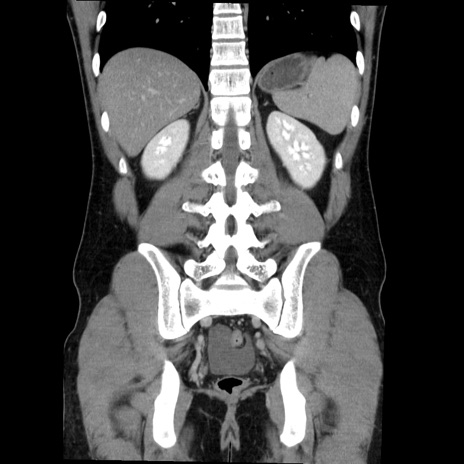

症例36(冠状断像)

【症例】20歳代 男性

【主訴】心窩部痛

【現病歴】今朝より上腹部痛あり。一旦軽快していたが再度出現したため救急要請。昨日夕に白身の魚を含む刺身を食べた。

【身体所見】BP 136/89mmHg、HR 74/min、BT 37.0℃、腹部:膨満、軟、心窩部に圧痛あり。反跳痛なし、筋性防御なし、腸雑音やや亢進あり。

【データ】WBC 17700、CRP 0.48